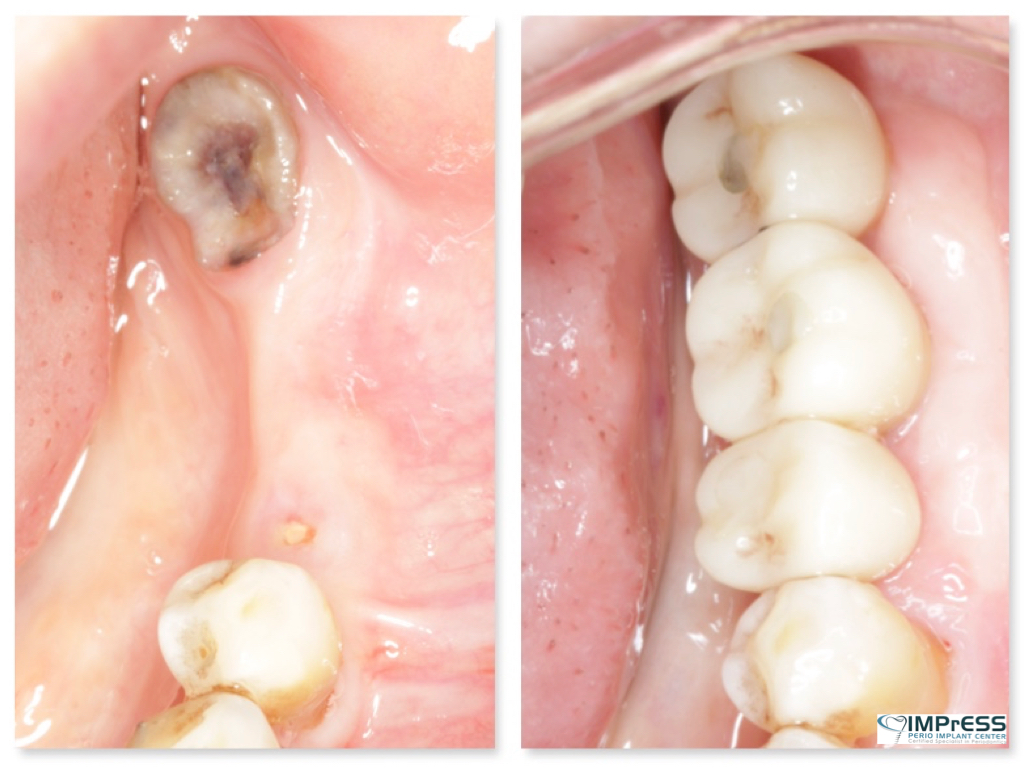

Immediate Implant Placement in Molar Extraction Site

immediate implant placement in molar site Dr. Noroozi